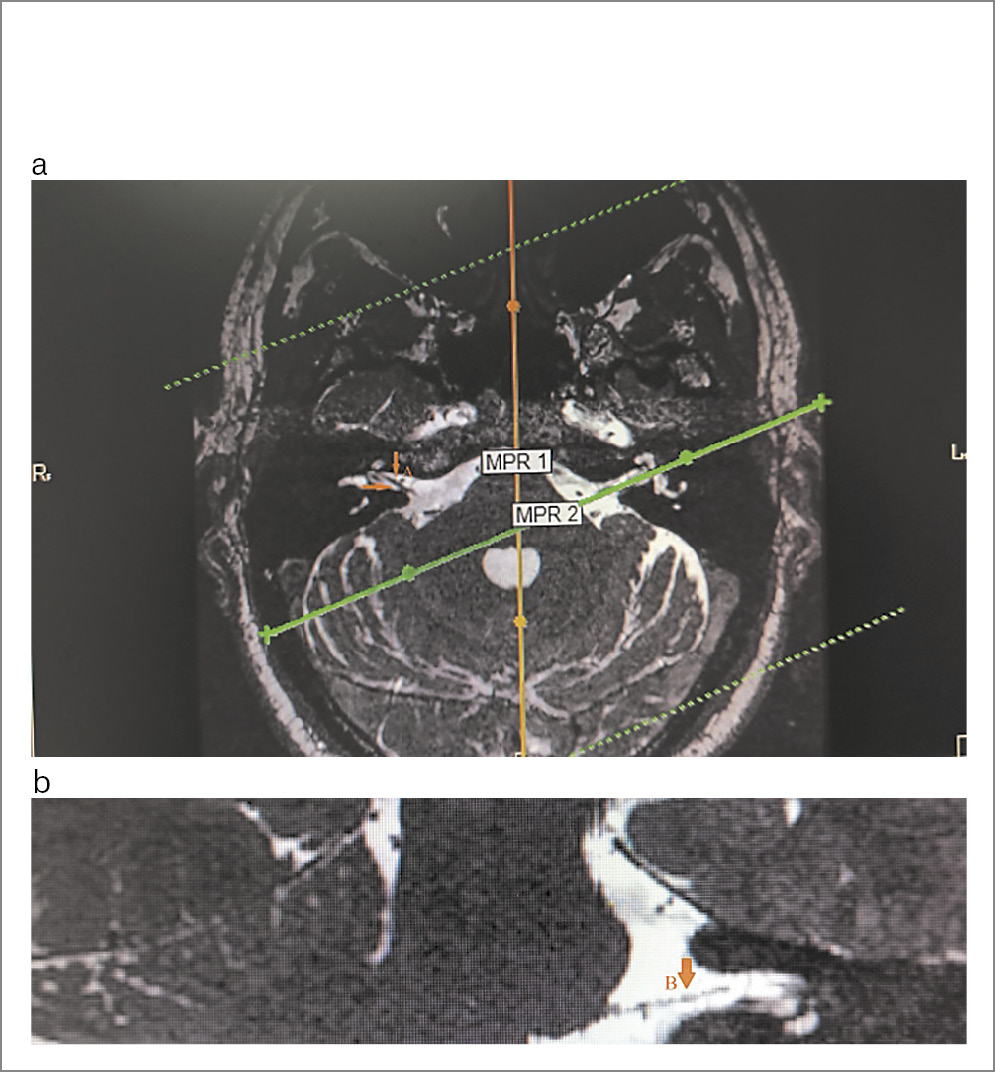

Лабораторно-инструментальные методы исследования: в клиническом и биохимическом анализах крови, общем анализе мочи отклонений от нормы не отмечено. По данным компьютерной томографии (КТ) височных костей патологических изменений в височных костях не выявлено (рис. 1). По данным КТ органов грудной клетки без патологических изменений очагового и/или инфильтративного характера в легких, верифицирован локальный участок пневмофиброза в верхней доле левого легкого; КТ-0. По результатам магнитно-резонансной томографии (МРТ) головного мозга обнаружены магнитно-резонансные признаки множественных очагов в белом веществе головного мозга (вероятнее всего, сосудистого характера), умеренного расширения субарахноидального пространства, низкое расположение миндалин мозжечка. Изменений в области мосто-мозжечкового угла не обнаружено (рис. 2, а, b). На магнитно-резонансной томографии черепных нервов с двух сторон визуализируется нормальный ход лицевых нервов (рис. 3). По данным ЭНМГ, выполненной на 5-е сутки от начала заболевания, определены признаки умеренно-выраженного поражения лицевого нерва слева. Характер поражения смешанный (поражение миелиновых оболочек и осевых цилиндров). Произвольная активация m. orbicularis oculi, m. orbicularis oris слева значительно снижена (рис. 4, а). Пациентка осмотрена оториноларингологом – данных за острую лор-патологию не выявлено, офтальмологом – OU «гипертоническая ангиопатия сетчатки».

Рис. 3. Лицевой нерв на МРТ черепных нервов: а – правый лицевой нерв; b – левый лицевой нерв.